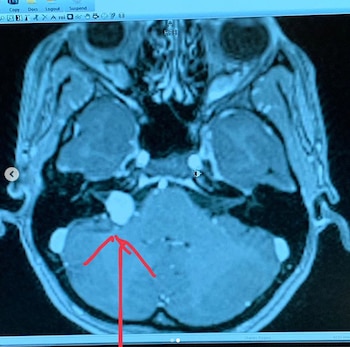

La madre de tres niños afirmó en las redes sociales que "ahora empieza una nueva" tras haber superado un neuroma acústico, tumor benigno, que le fue diagnosticado al inicio del año y que le provocaba fuertes episodios de vértigo. Posteriormente unos estudios revelaron que ella tenía un tumor en la cabeza y así lo confirmó a principios de este mes.

Kelly había revelado en otra publicación previa donde aparece junto a su pareja que el neuroma que sufría podía provocarle la pérdida del oído o algún tipo de desequilibrio. En esa misma imagen dijo por primera vez sobre su situación de salud y detalló que se dio cuenta de su problema mientras le enseñaba a su hijas movimientos de ballet.